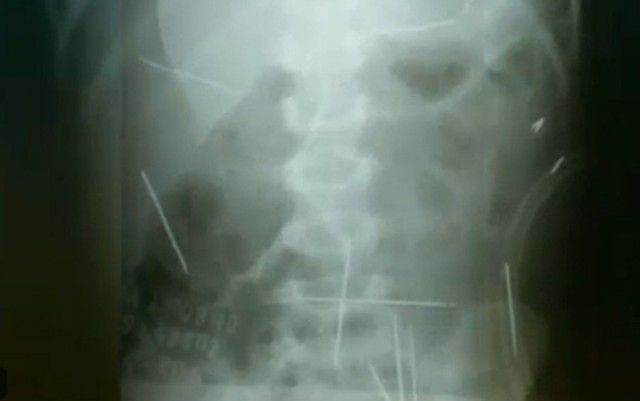

O caso aconteceu em Ibotirama, no oeste da Bahia, e ganhou repercussão no mundo inteiro. O garoto deu entrada no hospital chorando e sentindo muitas dores, quando tinha 2 anos e 7 meses. Sem diagnóstico evidente, os médicos pediram uma radiografia e encontraram as 31 agulhas espalhadas pelo corpo do menino.

Radiografia mostrou agulhas no corpo de criança; caso ocorreu em Ibotirama, na Bahia — Foto: Reprodução/TV Globo